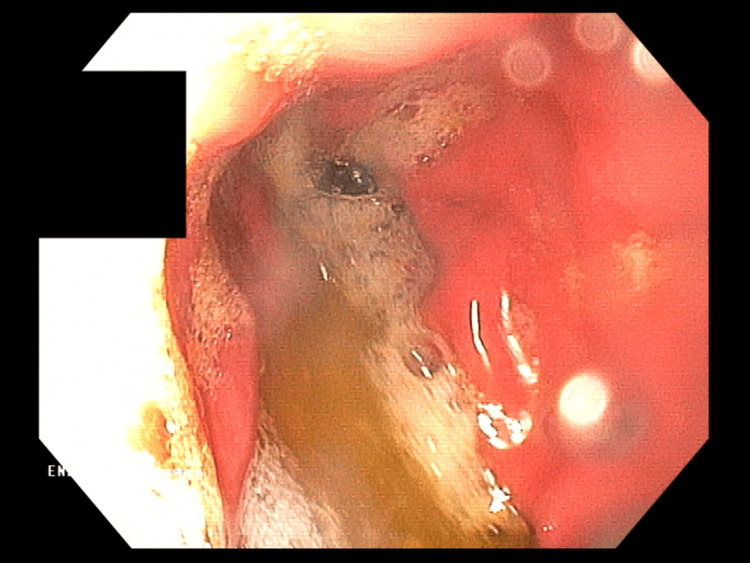

Symptomatic treatment (intravenous hydration, analgesic, and antiemetic treatment) was administered in the ward with good results. In the following days, a gradual resolution of symptoms was observed; the patient ate and drank willingly, did not report any complaints, and passed stools normally. During hospitalization, the diagnosis was expanded with gastrofiberoscopy, where erosive gastritis was described, and the Helicobacter pylori urease test result was negative (Figure 3). MRI of the head was performed, which was normal. In addition, the patient was screened for several metabolic diseases in various tests, including CoA medium-chain fatty acid dehydrogenase deficiency, tyrosinemia, maple syrup disease, hyperphenylalaninemia, and disorders of other amino acids metabolism.